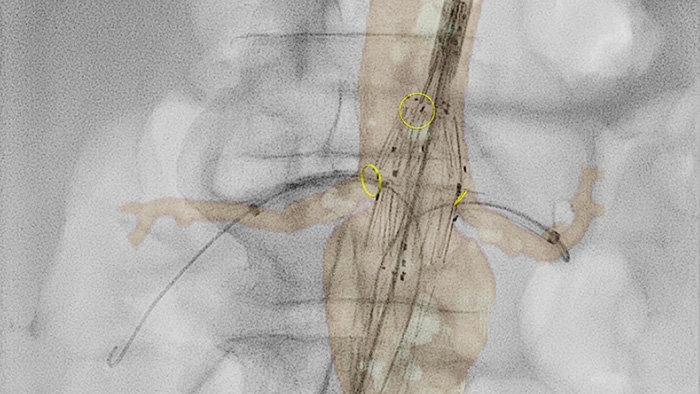

VesselNavigator permite reutilizar la información anatómica vascular 3D de conjuntos de datos de TAC y RM existentes como una superposición de mapa 3D sobre una imagen radiológica en tiempo real. Gracias a su excelente capacidad de visualización, VesselNavigator ofrece un mapa 3D intuitivo y continuo que le guiará por la vasculatura.